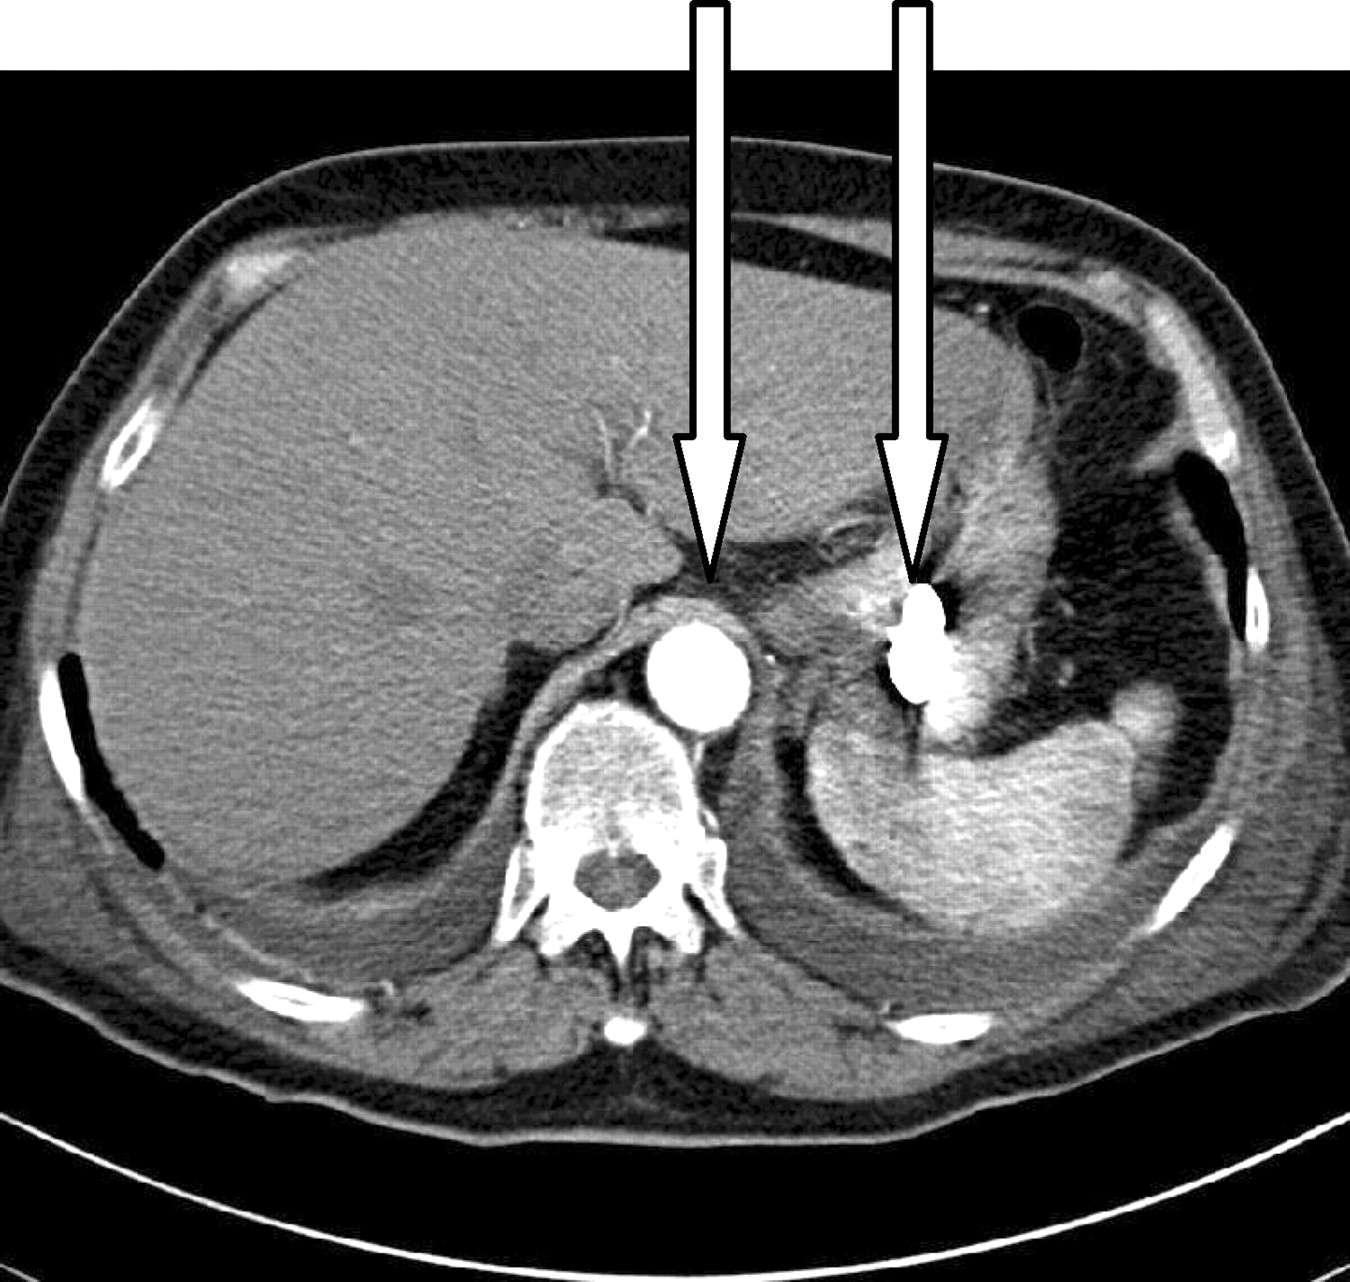

The answer to this mystery lay in her medications. She had been started on the phosphate binder lanthanum carbonate 3 months previously. Lanthanum is a rare earth metal which lies next to barium on the periodic table and has a high affinity for phosphate. It has little systemic absorption and low solubility and remains largely in the intestine after ingestion. It is a high density material with a density between that of bone and metal. The CT above shows lanthanum tablets in the stomach which have a higher density (3000HU) than the radiocontrast in the aorta (450HU). This accumulation appears to cause no ill effects and disappears once the drug is stopped or with the use of laxatives. The main issue is that it may interfere with the interpretation of xrays and radiologists should be informed that a patient is on this drug prior to abdominal imaging in order to prevent confusion.